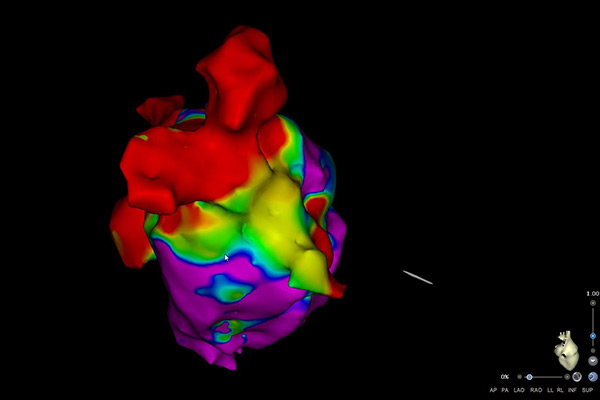

При електрофизиологичното изследване, посредством катетри (представляващи малки тръбички, които записват електрически сигнали) се прави точен запис на електрическите импулси в сърцето.

Изследването се извършва в т.нар. електрофизиологична лаборатория, в която се намира оборудването, необходимо за извършване на процедурата. В зависимост от аритмията се използва местна упойка, като при някои процедури се предпочита обща упойка (Вашият лекуващ лекар ще Ви уведоми за вида упойка, която ще бъде използвана). През вена на десния крак (понякога се налага използването на артерия) се въвеждат специални катетри (тръбички с диаметър под 3 мм), които записват директно електрическите сигнали от сърцето. По време на самото изследване сърцето се стимулира с електрически импулси, които Вие може да усетите като сърцебиене или по-силни сърдечни удари.

След като Вашият лекар е локализирал виновното за Вашата аритмия огнище се преминава към лечение – аблация. Посредством специален катетър се прилага енергия, наречена радиофреквентна енергия, която води до загряване и изгаряне на това огнище. Освен нагряване, при някои аритмии се използват специално пригодени балони или катетри, чрез които се постига замразяване на огнищата, водещи до аритмия, и тяхното елиминиране.